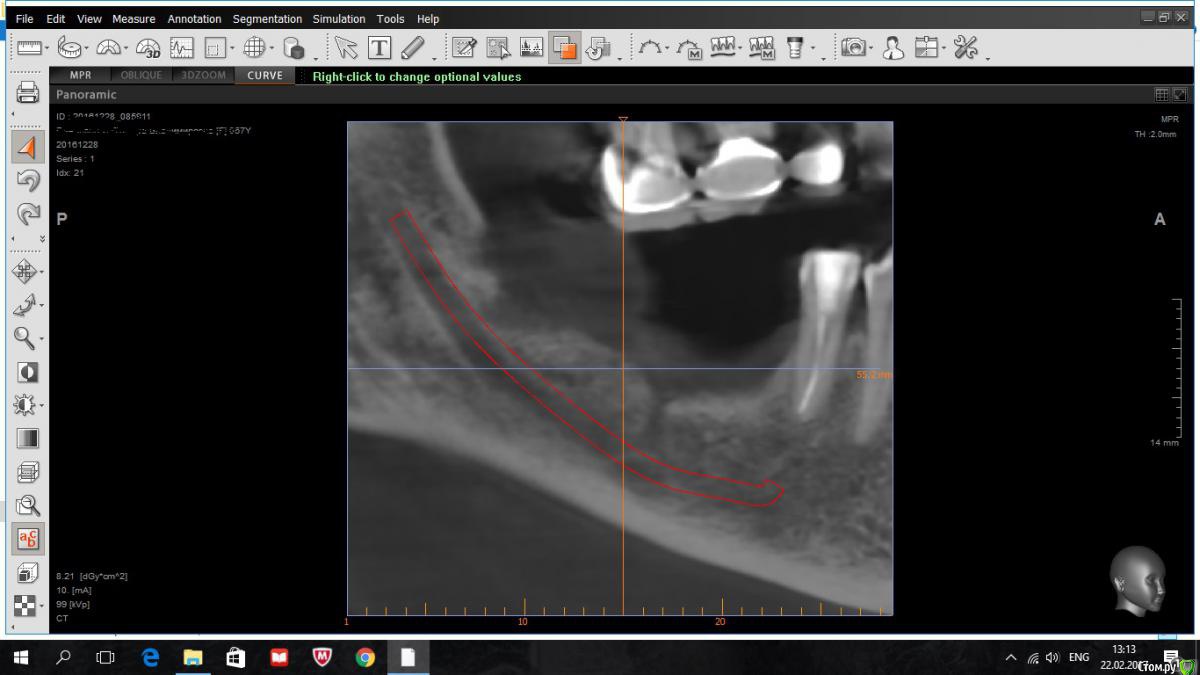

kriokov Опубликовано 22 февраля, 2017 Поделиться Опубликовано 22 февраля, 2017 . Не забуду если, завтра скрин кт залью.так примерно, это спустя семь лет после "неприживления" пластинки Ссылка на комментарий